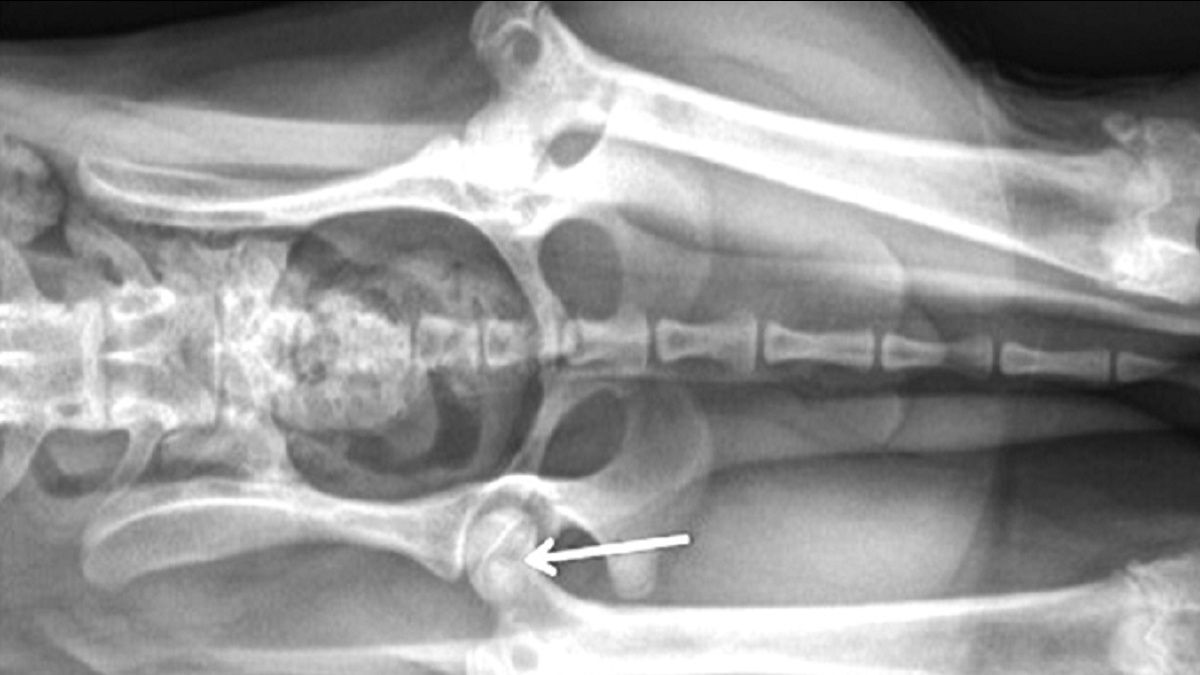

Aunque con la exploración física y la reseña del paciente se puede sospechar firmemente una ELCP, para poder confirmar el diagnóstico suele ser necesario el estudio radiológico. En las fases iniciales se pueden observar áreas de lisis y desmineralización en la región subcondral de la cabeza y cuello del fémur (Figura 1). A medida que la enfermedad avanza, puede evidenciarse el colapso de la cabeza y cuello femoral (Figura 2). Después, en fases más tardías, es posible observar la remineralización y la cicatrización ósea. También pueden presentarse alteraciones indicativas de una osteoartritis secundaria, que incluyen la formación de osteofitos (especialmente en el borde acetabular dorsal) y el aplanamiento de la cabeza femoral.

Radiografía en la que se muestran las alteraciones típicas del inicio de la ELCP en un perro. La flecha indica las áreas de desmineralización precoz.

Figura 1. Radiografía en la que se muestran las alteraciones típicas del inicio de la ELCP en un perro. La flecha indica las áreas de desmineralización precoz.© Darryl L. Millis